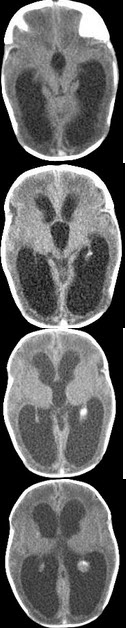

1岁,女,头颅呈球状,颅骨透光试验阳性,请结合CT图片,选择最可能的诊断( )

A:脑严重缺血

B:慢性双侧性巨大硬膜下血肿

C:水瘤

D:先天性脑积水

E:重度脑积水